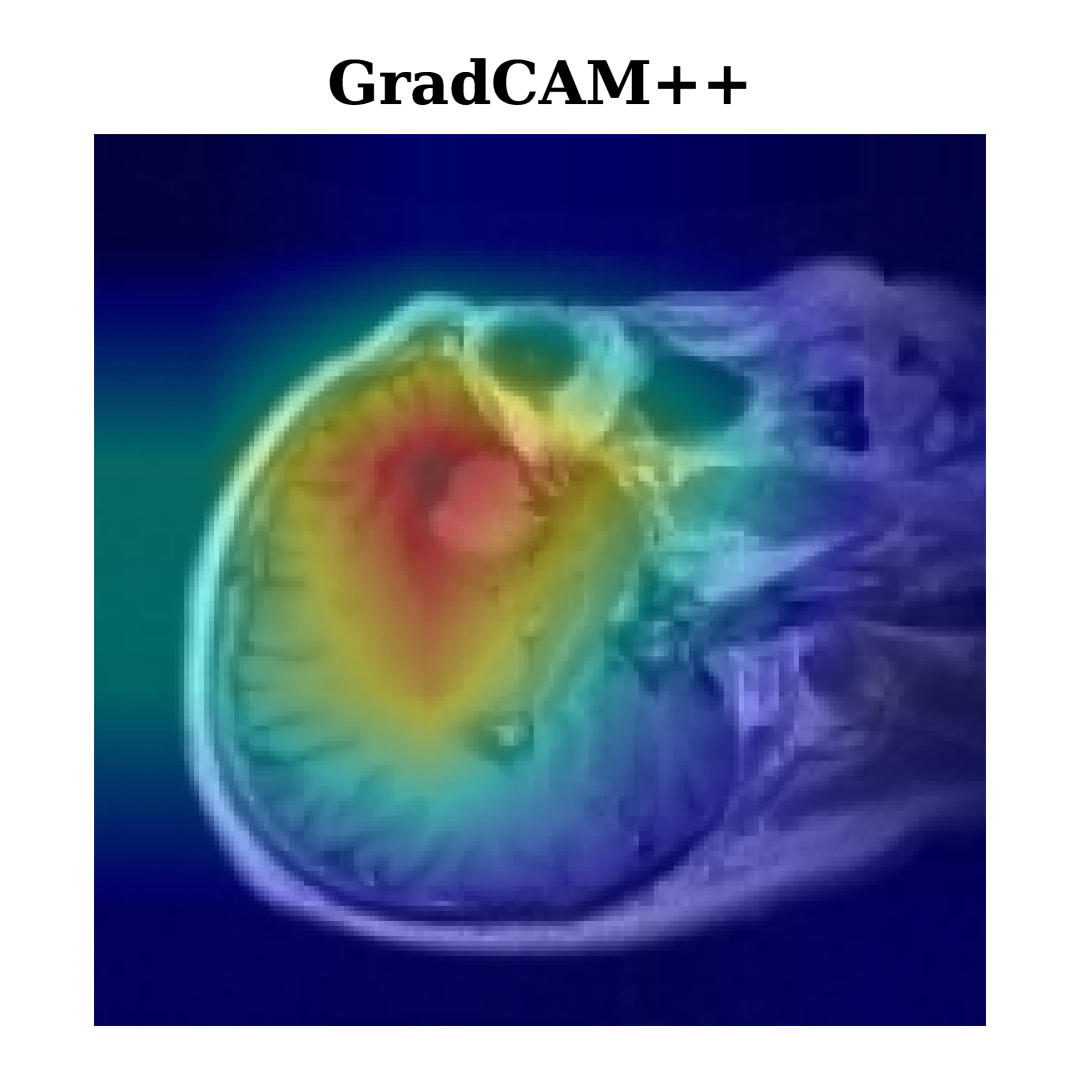

XAI includes techniques designed to enhance the transparency and interpretability of AI model decisions, hence making complex models more understandable to humans. Techniques like Grad-CAM and Grad-CAM++ highlight image areas that significantly influence a model’s output, helping users see which data aspects affect its predictions.

Grad-CAM and Grad-CAM++ are interpretability methodologies extensively employed in deep learning to visualize the critical areas of an input image that substantially influence a model’s classification result. Grad-CAM [16] functions by calculating the gradient of the class score YcY^{c} with respect to the feature maps AkA^{k}. The gradients are globally averaged to obtain significant weights αkc\alpha_{k}^{c} for each feature map AkA^{k}. The resultant weighted sum of the feature maps undergoes a ReLU activation to generate a heatmap that emphasizes the significant areas of the image. The equation for Grad-CAM [17] can be written as:

Grad-CAM++ [18] enhances this process by incorporating second-order derivatives, allowing for more precise localization of important regions in the image. Grad-CAM++ refines the weighting scheme, taking into account both first-order and second-order gradients for greater interpretability, especially when multiple objects or patterns are present in the image. The formula for Grad-CAM++ is expressed as:

By leveraging these higher-order gradients, Grad-CAM++ generates a more detailed and accurate heatmap, making it particularly effective for images with multiple objects or complex patterns, offering refined interpretability compared to Grad-CAM. Figure 5 demonstrates the utilization of Grad-CAM and Grad-CAM++ in our research, augmenting the interpretability of brain tumor classifications by offering critical insights into the decision-making processes of our deep learning models for tumor types including Menin, Glioma, and Tumor. Both techniques consistently capture similar critical regions, focusing on areas around the tumor’s core where distinguishing features are most prominent, thus supporting the reliability of model predictions across different tumor types.

Grad-CAM++ further refines these regions with more precise localization, particularly in complex cases like Glioma, where subtle boundaries exist between tumor and healthy tissue. This overlap in identified regions validates their importance for classification, with Grad-CAM++ offering a finer resolution that reveals deeper insights into tumor morphology. Comparing these XAI techniques provides a clearer understanding of feature importance by highlighting both similar and distinct regions, which strengthens interpretability and model transparency. This approach not only validates the model’s predictions but also enhances trust in AI as a precise and reliable tool in complex medical diagnostics, reinforcing its value in understanding tumor structures.